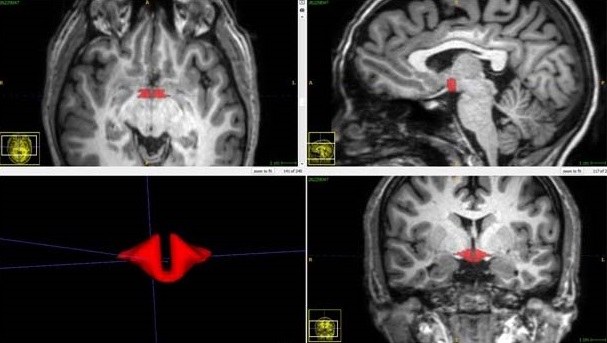

Pigułki hormonalne są jednymi z najbardziej popularnych środków antykoncepcyjnych, ale obecnie stosuje się je także w przypadkach różnych zaburzeń, jak nieregularne miesiączki, trądzik, endometrioza czy zespół wielotorbielowatych jajników. Prof. Lipton wraz ze współpracownikami zaprosił do udziału w eksperymencie grupę 50 zdrowych kobiet, z których 21 używało doustnej antykoncepcji. U wszystkich przeprowadzono nieinwazyjne badanie struktury mózgu w wykorzystaniem aparatury obrazowania z pomocą Magnetycznego Rezonansu Jądrowego (MRI). Objętość podwzgórza zmierzono z pomocą nowych, opracowanych przez autorów metod analizy obrazu.

Odkryliśmy dramatyczne różnice objętości tej struktury mózgu między kobietami, które stosują pigułkę antykoncepcyjną i tymi, które jej nie zażywają - mówi prof. Lipton. Te wstępne badania wskazują na silny związek jednego z drugim i powinny być motywacją do dalszych badań wpływu doustnej antykoncepcji na strukturę mózgu i ewentualnie także jego funkcje - tłumaczy. Autorzy przyznają, że wstępne wyniki analizy wpływu zmniejszonej objętości podwzgórza na pracę mózgu nie wykazują obniżenia funkcji poznawczych, sugerują jednak, że może mieć znaczenie dla kontroli emocji i pojawiania się objawów depresji.